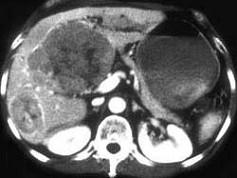

女,67岁,右上腹疼痛,消瘦4个月余,CT检查如图,最可能的诊断是 ( )A、肝转移瘤B、肝囊肿C、肝脓肿D、肝癌E、肝血管瘤

问题 女,67岁,右上腹疼痛,消瘦4个月余,CT检查如图,最可能的诊断是 ( )

选项 A、肝转移瘤 B、肝囊肿 C、肝脓肿 D、肝癌 E、肝血管瘤

答案 D